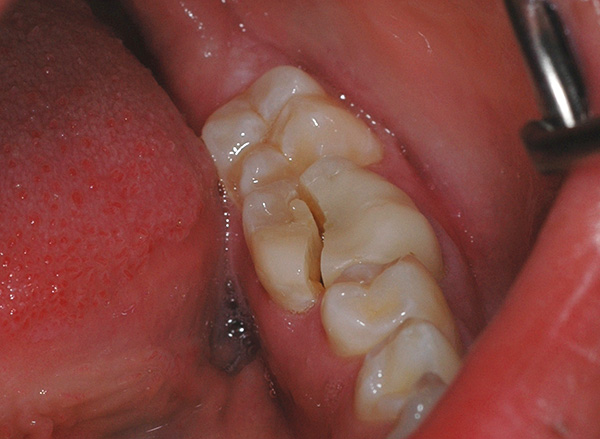

- Con fratture complesse del dente (ad esempio, con una longitudinale - vedi l'esempio nella foto sotto);

- Sullo sfondo di gravi processi infiammatori vicino alla radice (grande cisti, periostite, osteomielite, ascesso, flemmone);

- La distruzione della corona del dente è molto più bassa del livello delle gengive;

- Mobilità radicale di III grado;

- Posizione atipica del dente distrutto (varie dentature).

Tuttavia, come già notato sopra, lontano da ogni frattura del dente, le radici rimanenti devono essere rimosse. Una scheggia può dividere sia da un dente vivo che da un dente morto, cioè precedentemente depulso, e i morti sono più vulnerabili a questo proposito, poiché diventano fragili nel tempo. Quindi, se la radice non è molto colpita e ha una solida base, il dente viene ripristinato con metodi convenzionali: il canale viene trattato (se il dente era vivo) e la corona viene ripristinata mediante restauro o protesi.

Le fotografie seguenti mostrano l'estrazione del dente, la cui parte della corona viene distrutta quasi al livello delle gengive: